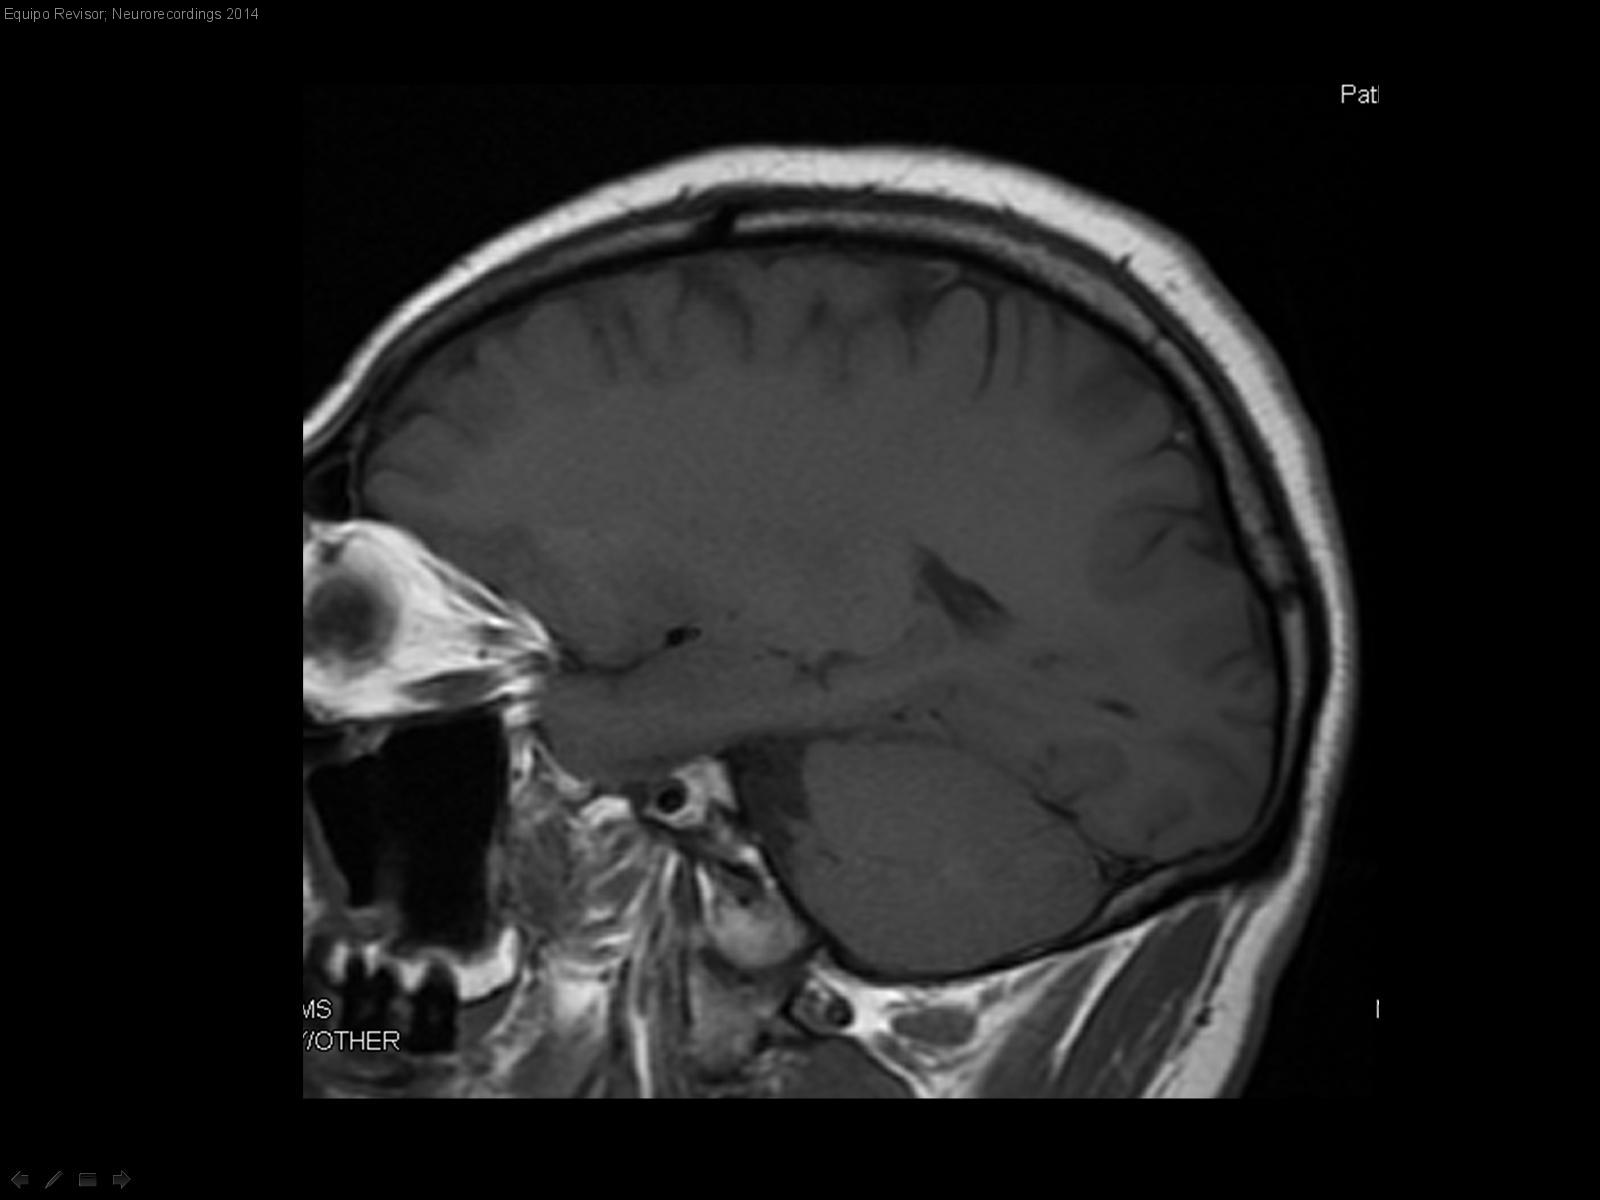

Hombre | 42 años

Diagnóstico final: Quiste Cisura Coroidea

Quiste cisura coroidea como hallazgo en TAC solicitado por cefalea